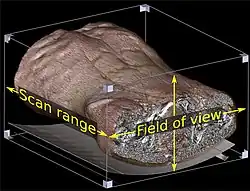

3D rendering of a μCT scan of a leaf piece, resolution circa 40 μm/voxel when viewed at the full size

The value of a voxel may represent various properties. In CT scans, the values are Hounsfield units, giving the opacity of material to X-rays.[14]: 29 Different types of value are acquired from MRI or ultrasound.